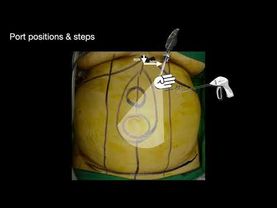

eTEP RS Ventral Hernia Repair by Optical entry & 3 Port | Step by step narration | Dr.Parveen Bhatia

Download information and video details for eTEP RS Ventral Hernia Repair by Optical entry & 3 Port | Step by step narration | Dr.Parveen Bhatia